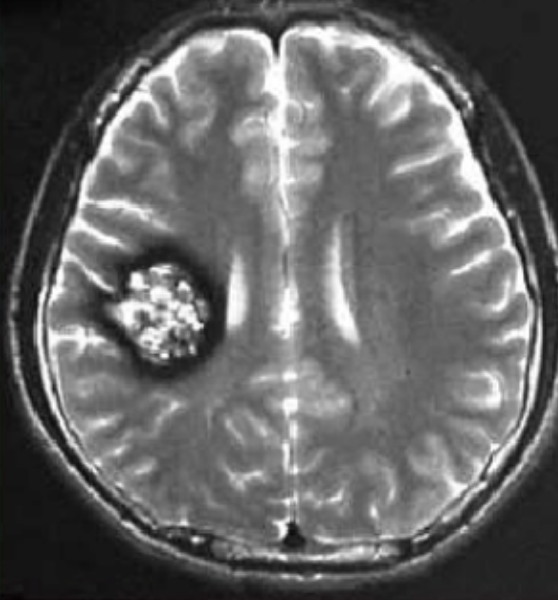

腦干海綿狀血管瘤